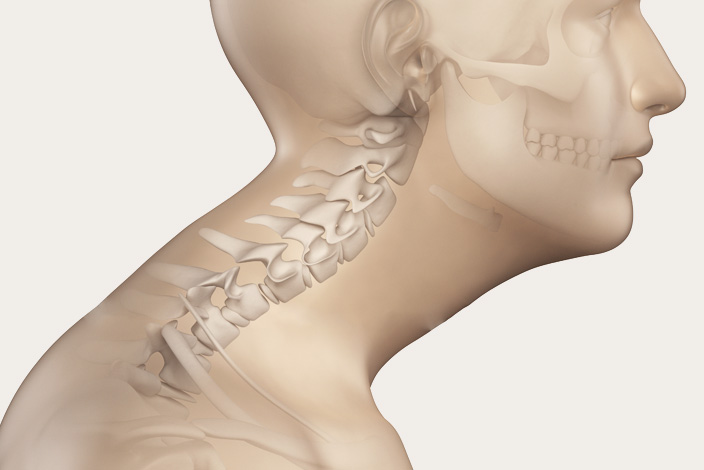

우선 목디스크란 목뼈 사이의 디스크가 깨지거나 상해 일어나는 질환을 의미합니다. 디스크는 척추뼈 사이에서 충격을 흡수하고 신경을 보호해주는 역할을 하는데, 디스크가 손상되면 신경이 압박되어 통증, 저림, 마비 등의 증상이 보여집니다.

우리의 목은 인체에서 무척 요긴한 역할을 합니다. 머리를 지지하여 돕고, 머리를 움직여 시야를 확보하는 역할을 히며, 척추의 시작 부분으로서 척추를 지켜주고, 척추를 통해 뇌와 인체의 다른 부분으로 신경을 보급하는 역할을 합니다.